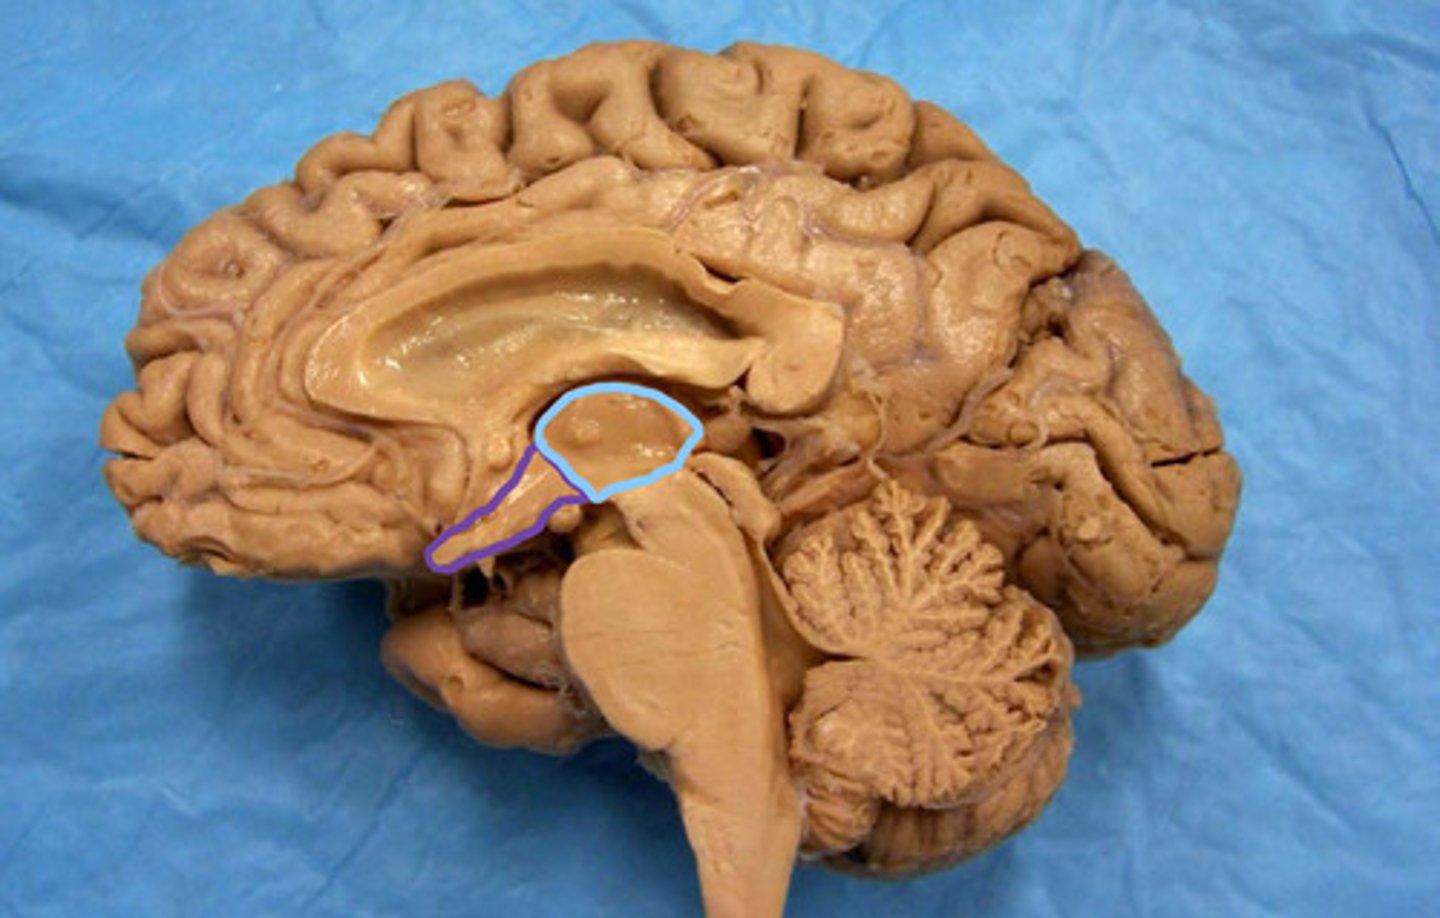

blue - thalamus

purple - hypothalamus

identify the structures

thalamus

identify the structure